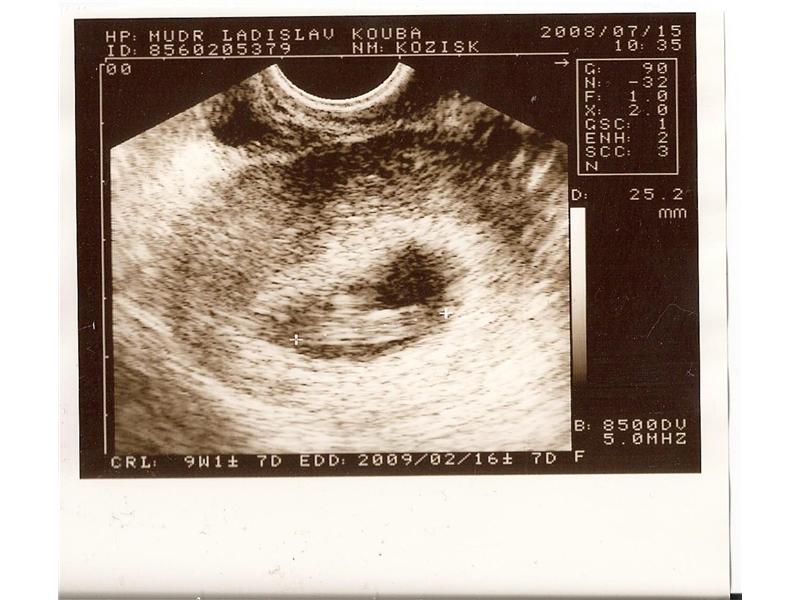

10.týden

2 fotografií